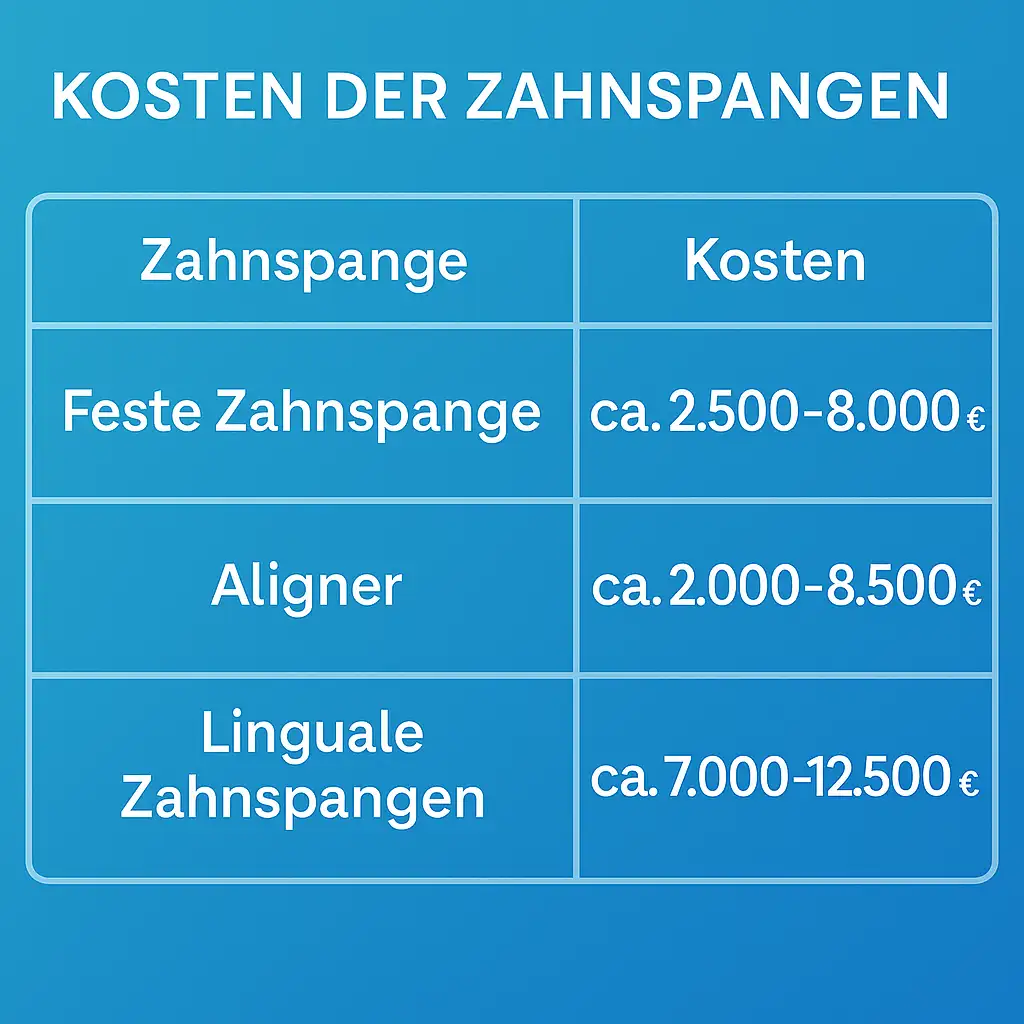

Die Kosten variieren je nach Methode:

Leichte Korrekturen mit Aligner:

ab 2000 – 8000 €

Feste Spangen:

2500 – 8000 €

Lingualtechnik:

7000 – 10000+ €

Kombinierte chirurgische Eingriffe:

>10.000 €

Kosten für Zahnspangen im Überblick: Feste Zahnspange ca. 2.500–8.000 €, Aligner ca. 2.000–8.500 €, linguale Zahnspangen ca. 7.000–12.500 €.

Die Kosten einer kieferorthopädischen Behandlung variieren stark. Sie hängen von der Art der Fehlstellung, der gewählten Behandlungsmethode und der Dauer der Therapie ab.

Typische kleinere Korrekturen beginnen bei etwa 2.000 Euro, während eine festsitzende Spange im Schnitt bei 2.500 Euro startet. Komplexe Kiefergelenksdefekte können 6.000 Euro oder mehr kosten. Aligner‑Systeme und die Lingualtechnik sind häufig teurer als klassische Brackets.